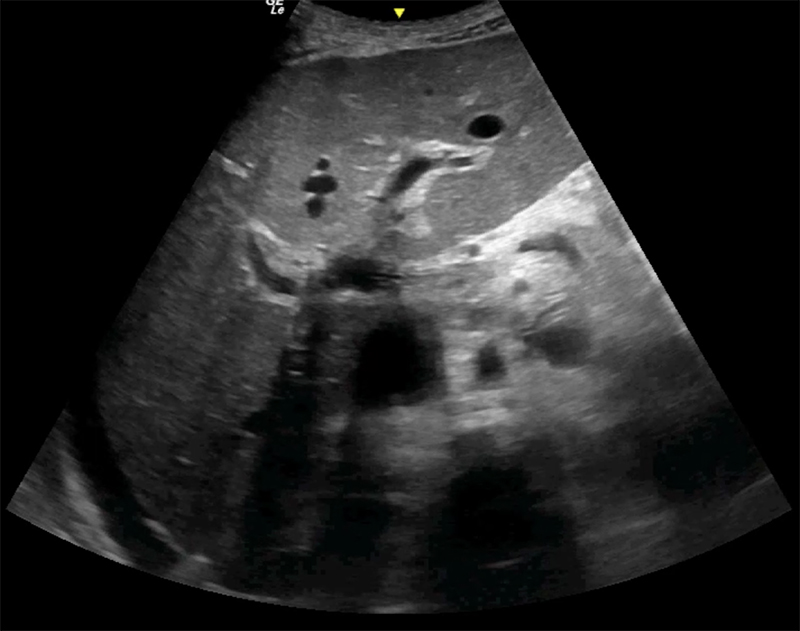

Figure 54A. Transverse views of the liver revealing moderate periportal fibrosis. Note the thickened hyperechoic walls surrounding the portal vein and branches.

Figure 54B. Transverse views of the liver revealing moderate periportal fibrosis. Note the thickened hyperechoic walls surrounding the portal vein and branches.